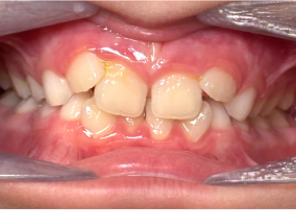

Étude de cas 1

10 ans et 0 mois, 18 étapes d’appareils d’expansion palatine Invisalign

Avec l’aimable autorisation de la Dre Sandra Khong Tai

Avant le traitement d’expansion avec les appareils d’expansion palatine Invisalign

Après le traitement d’expansion avec les appareils d’expansion palatine Invisalign

Après le traitement Invisalign First